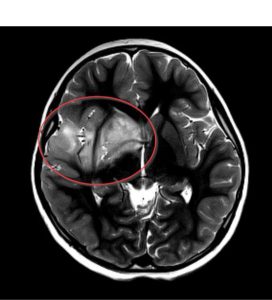

- Обнаружение патологий: МРТ позволяет выявить различные патологические изменения, такие как опухоли, воспалительные процессы, травмы и деформации. Врач оценивает характер этих изменений и их влияние на здоровье пациента.

- Оценка состояния тканей: С помощью МРТ врач может оценить состояние различных тканей, включая мягкие ткани, кости, суставы и сосуды. Это позволяет выявить дегенеративные изменения, дисплазии, аномалии развития и другие патологии.

- Функциональные аспекты: Некоторые исследования МРТ могут оценивать функциональную активность органов, таких как мозг или сердце, путем изучения кровотока, активации определенных областей и других параметров.